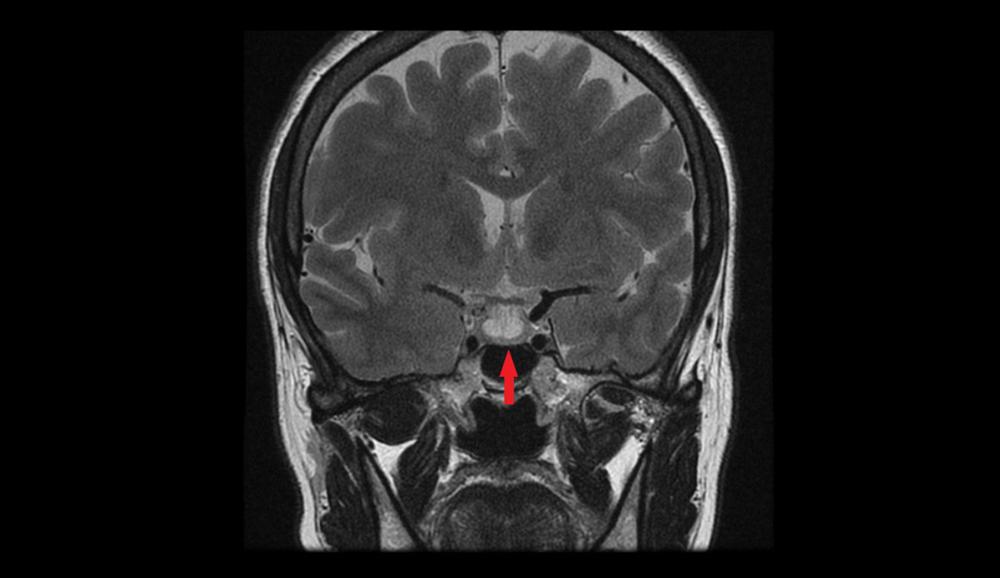

- Pencitraan otak, seperti MRI atau CT scan kepala, untuk mendeteksi tumor pituitari.